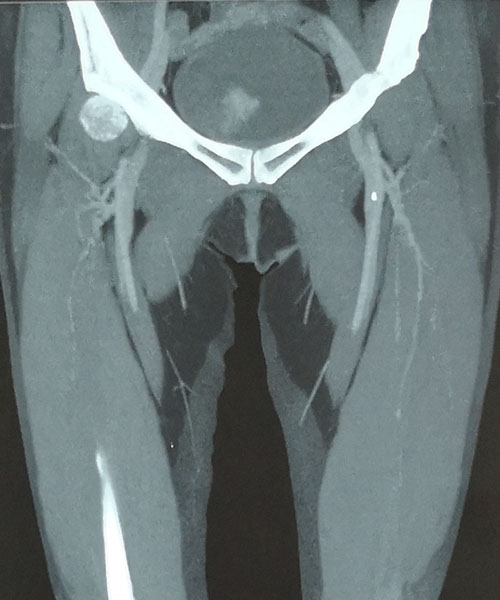

術(shù)前CTV評(píng)估股靜脈及分支